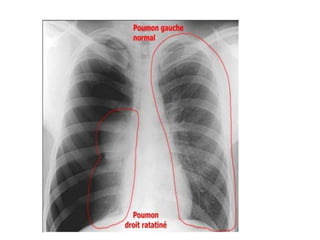

1. LA RX STANDARD DU THORAX

LA RX STANDARD DU THORAX

Résultats :

• hyperclarté avasculaire homogène périphérique

prenant tout l’hémithorax plus ou moins étendue.

• Rétraction du poumon s/f d’un moignon hyperdense

sur le hile avec distension des EIC et une netteté

anormale des côtes.

• La plèvre viscérale qui entoure ce moignon apparaît

sous forme d’un fin liséré opaque net comme tracé au

crayon